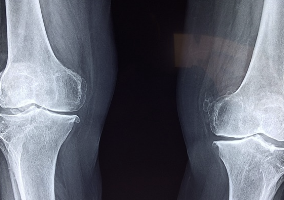

MSM(Methylsulfonylmethane)은 유기 화합물로서, 유독성이 낮고 천연으로 발생하는 화합물입니다. MSM은 각종 질병 및 부상 치료를 위해 사용되며, 특히 연골 및 관절 건강에 대한 효과로 인해 관심을 받고 있습니다. MSM은 화학적으로 일종의 황으로 구성되어 있으며, 식이 보충제로 섭취될 때 신체 내부에 있는 연골 및 관절과 같은 조직에 흡수됩니다. 이로 인해 MSM은 관절 통증, 염좌, 건염, 근육 부상, 긴장, 피로 및 손상을 예방하고 치료하는 데 도움이 됩니다.